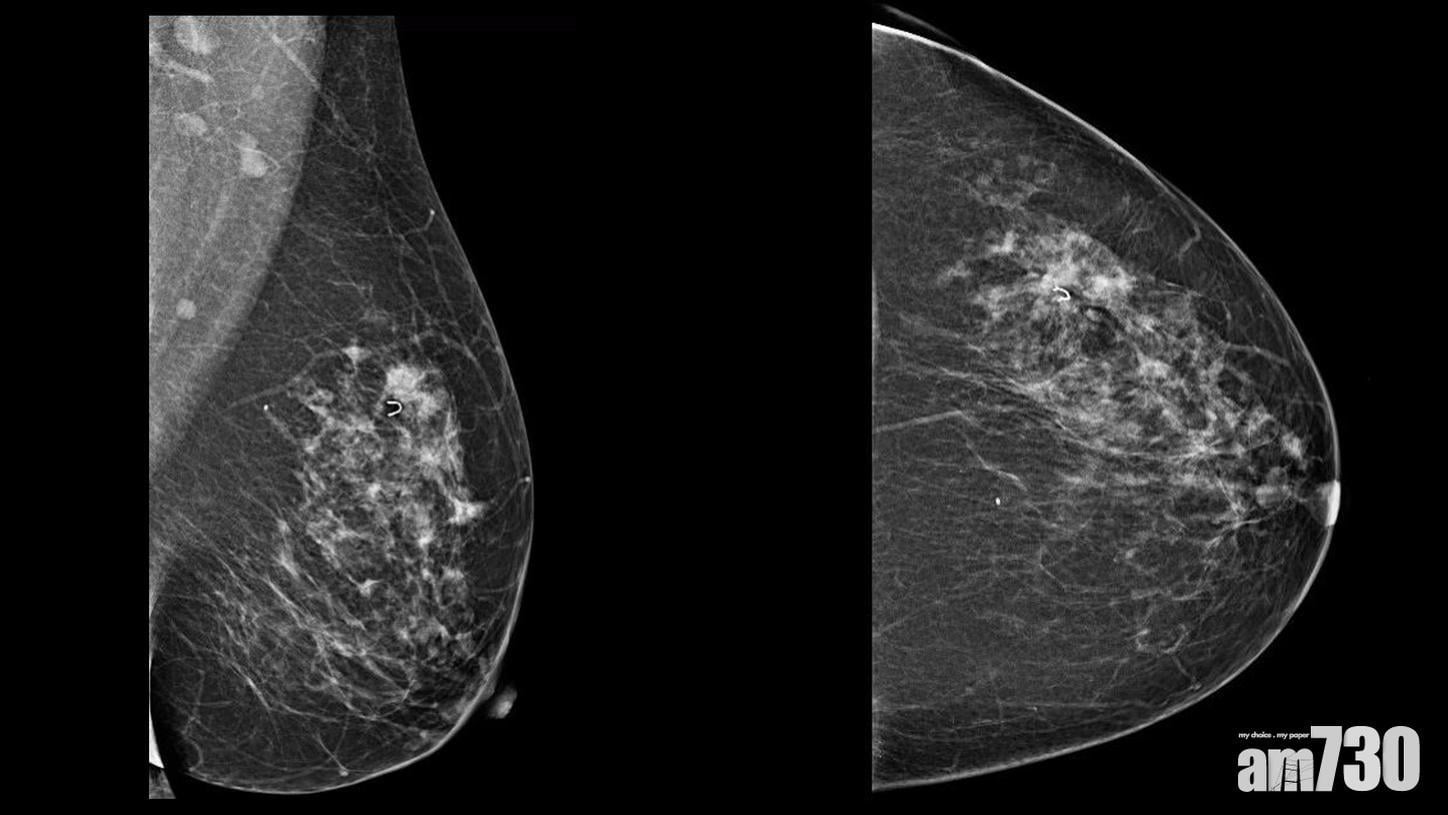

乳癌篩查先導計劃主要用乳房X光造影檢查,以及輔助性超聲波乳房檢查。前者可以清楚呈現乳房組織,若出現微鈣化點或異常情況,醫生一般會講解及跟進。如果乳房組織的密度較,如40歲或以下女性,或須輔以超聲波乳房檢查。另一方面,觸診有腫塊而X光片看不到、X光發現有腫塊並要確面硬塊還是囊腫、抽取組織時作引導,都會用到超聲波。現時乳房磁力共振掃描亦會用於高風險女性,惟未包括在是次先導計劃當中。

乳房X光造影檢查可清晰顯示乳腺組織。